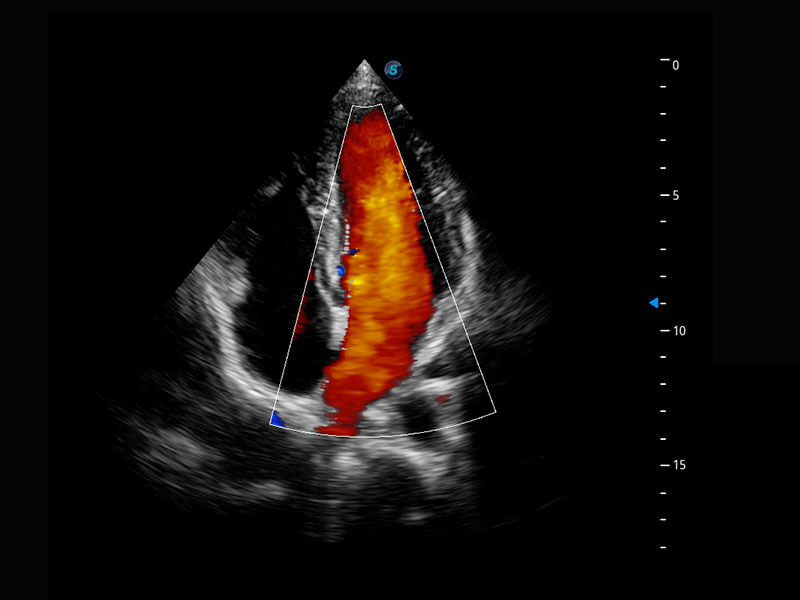

乳腺超声 / 新生儿

P60搭载宽频带线阵探头、宽景成像、弹性成像技术,为您提供乳腺应用方案。P60支持高频相控阵探头、线阵探头、腹部高频探头、腹部微凸探头等,丰富的探头群搭载敏感的彩色血流成像,适用于新生儿多种脏器检测要求,满足新生儿筛查需求。

• 新生儿肝血管癌

• 新生儿心脏